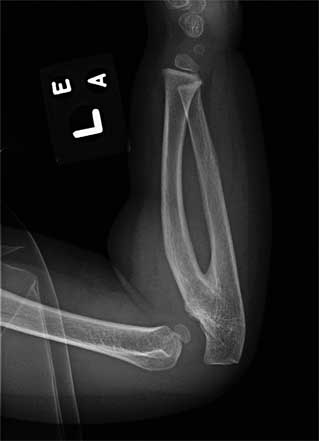

Очевидно, что немаловажную роль сыграл и случай с ребенком с диагнозом радиоульнарный синостоз. Это аномалия развития возникает в результате нарушения процесса внутриутробного развития малыша, когда нарушается процесс апоптоза – то есть процесс разделения лучевой и локтевой костей.

На иллюстрации справа пример синостоза сверху и нормы снизу:

Одним из пациентов на показательном сеансе Виолы Фрайман и был ребенок с этим диагнозом. Каково же было удивление врачей-ортопедов, когда примерно через 10 месяцев произошло сегментирование костей предплечья, и объем движения полностью восстановился! На последующие въедливые расспросы врачей Виола отвечала: «Я только освободила дорогу жизненным силам, а все остальное организм сделал сам».